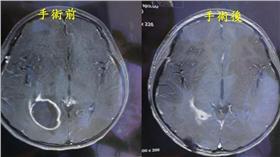

腦膿瘍

男「先昏後倒」急診 原來是腦膿瘍…

64歲紀先生昏倒送至某醫學中心急診,診斷為少量左側硬...

活潑女童個性驟變 原來是腦膿瘍作祟

一名10歲葉姓女童原本活潑開朗,近期卻出現嗜睡、頭痛...